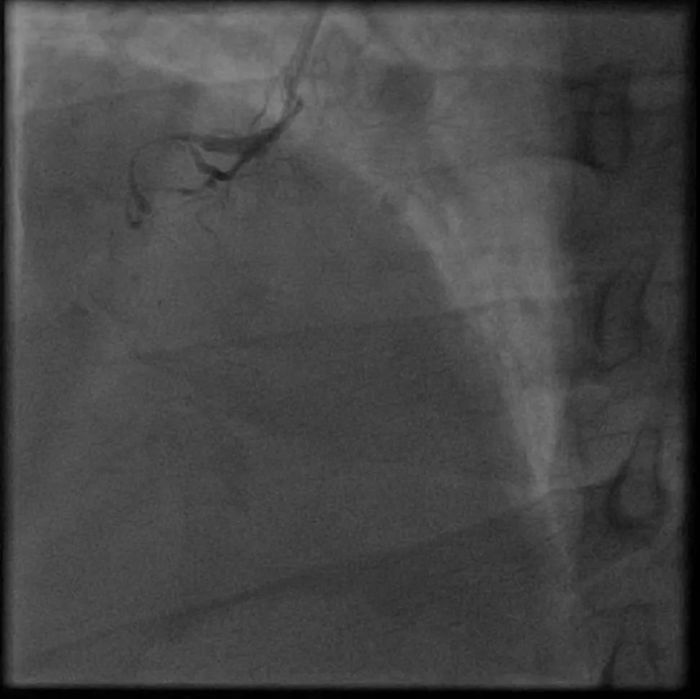

唐先生因为急性胸痛到桂林市某三甲医院诊断急性心梗,冠脉造影检查提示RCAp(右冠状动脉近段)慢性闭塞,LMd(左主干远端)95%狭窄,血管病变极为严重,支架手术风险极大,该院建议冠脉手术搭桥。

为了满足患者及家属的愿望,提高年轻患者的生活质量,延长患者的生命,王新云团队为患者进行了周详的术前准备,因为唐先生右冠闭塞,左侧无保护病变,在充分评估手术风险以及与患者家属充分沟通后,决定分两期为他实施手术。第一次手术----右冠CTO病变的处理,手术过程十份艰难,面对这样复杂的病变,王新云熟练地操作着微导管、穿通导管、导引延伸导管及多种CTO导丝。手术非常顺利,成功地开通了右冠脉的CTO病变,并在血管内超声(IVUS)的指导下顺利植入了支架。有了这支血管的保驾护航,再次为患者实施了第二次手术:左主干+前三叉血管病变处理,两期手术都获得巨大成功,让唐先生重获了新生。